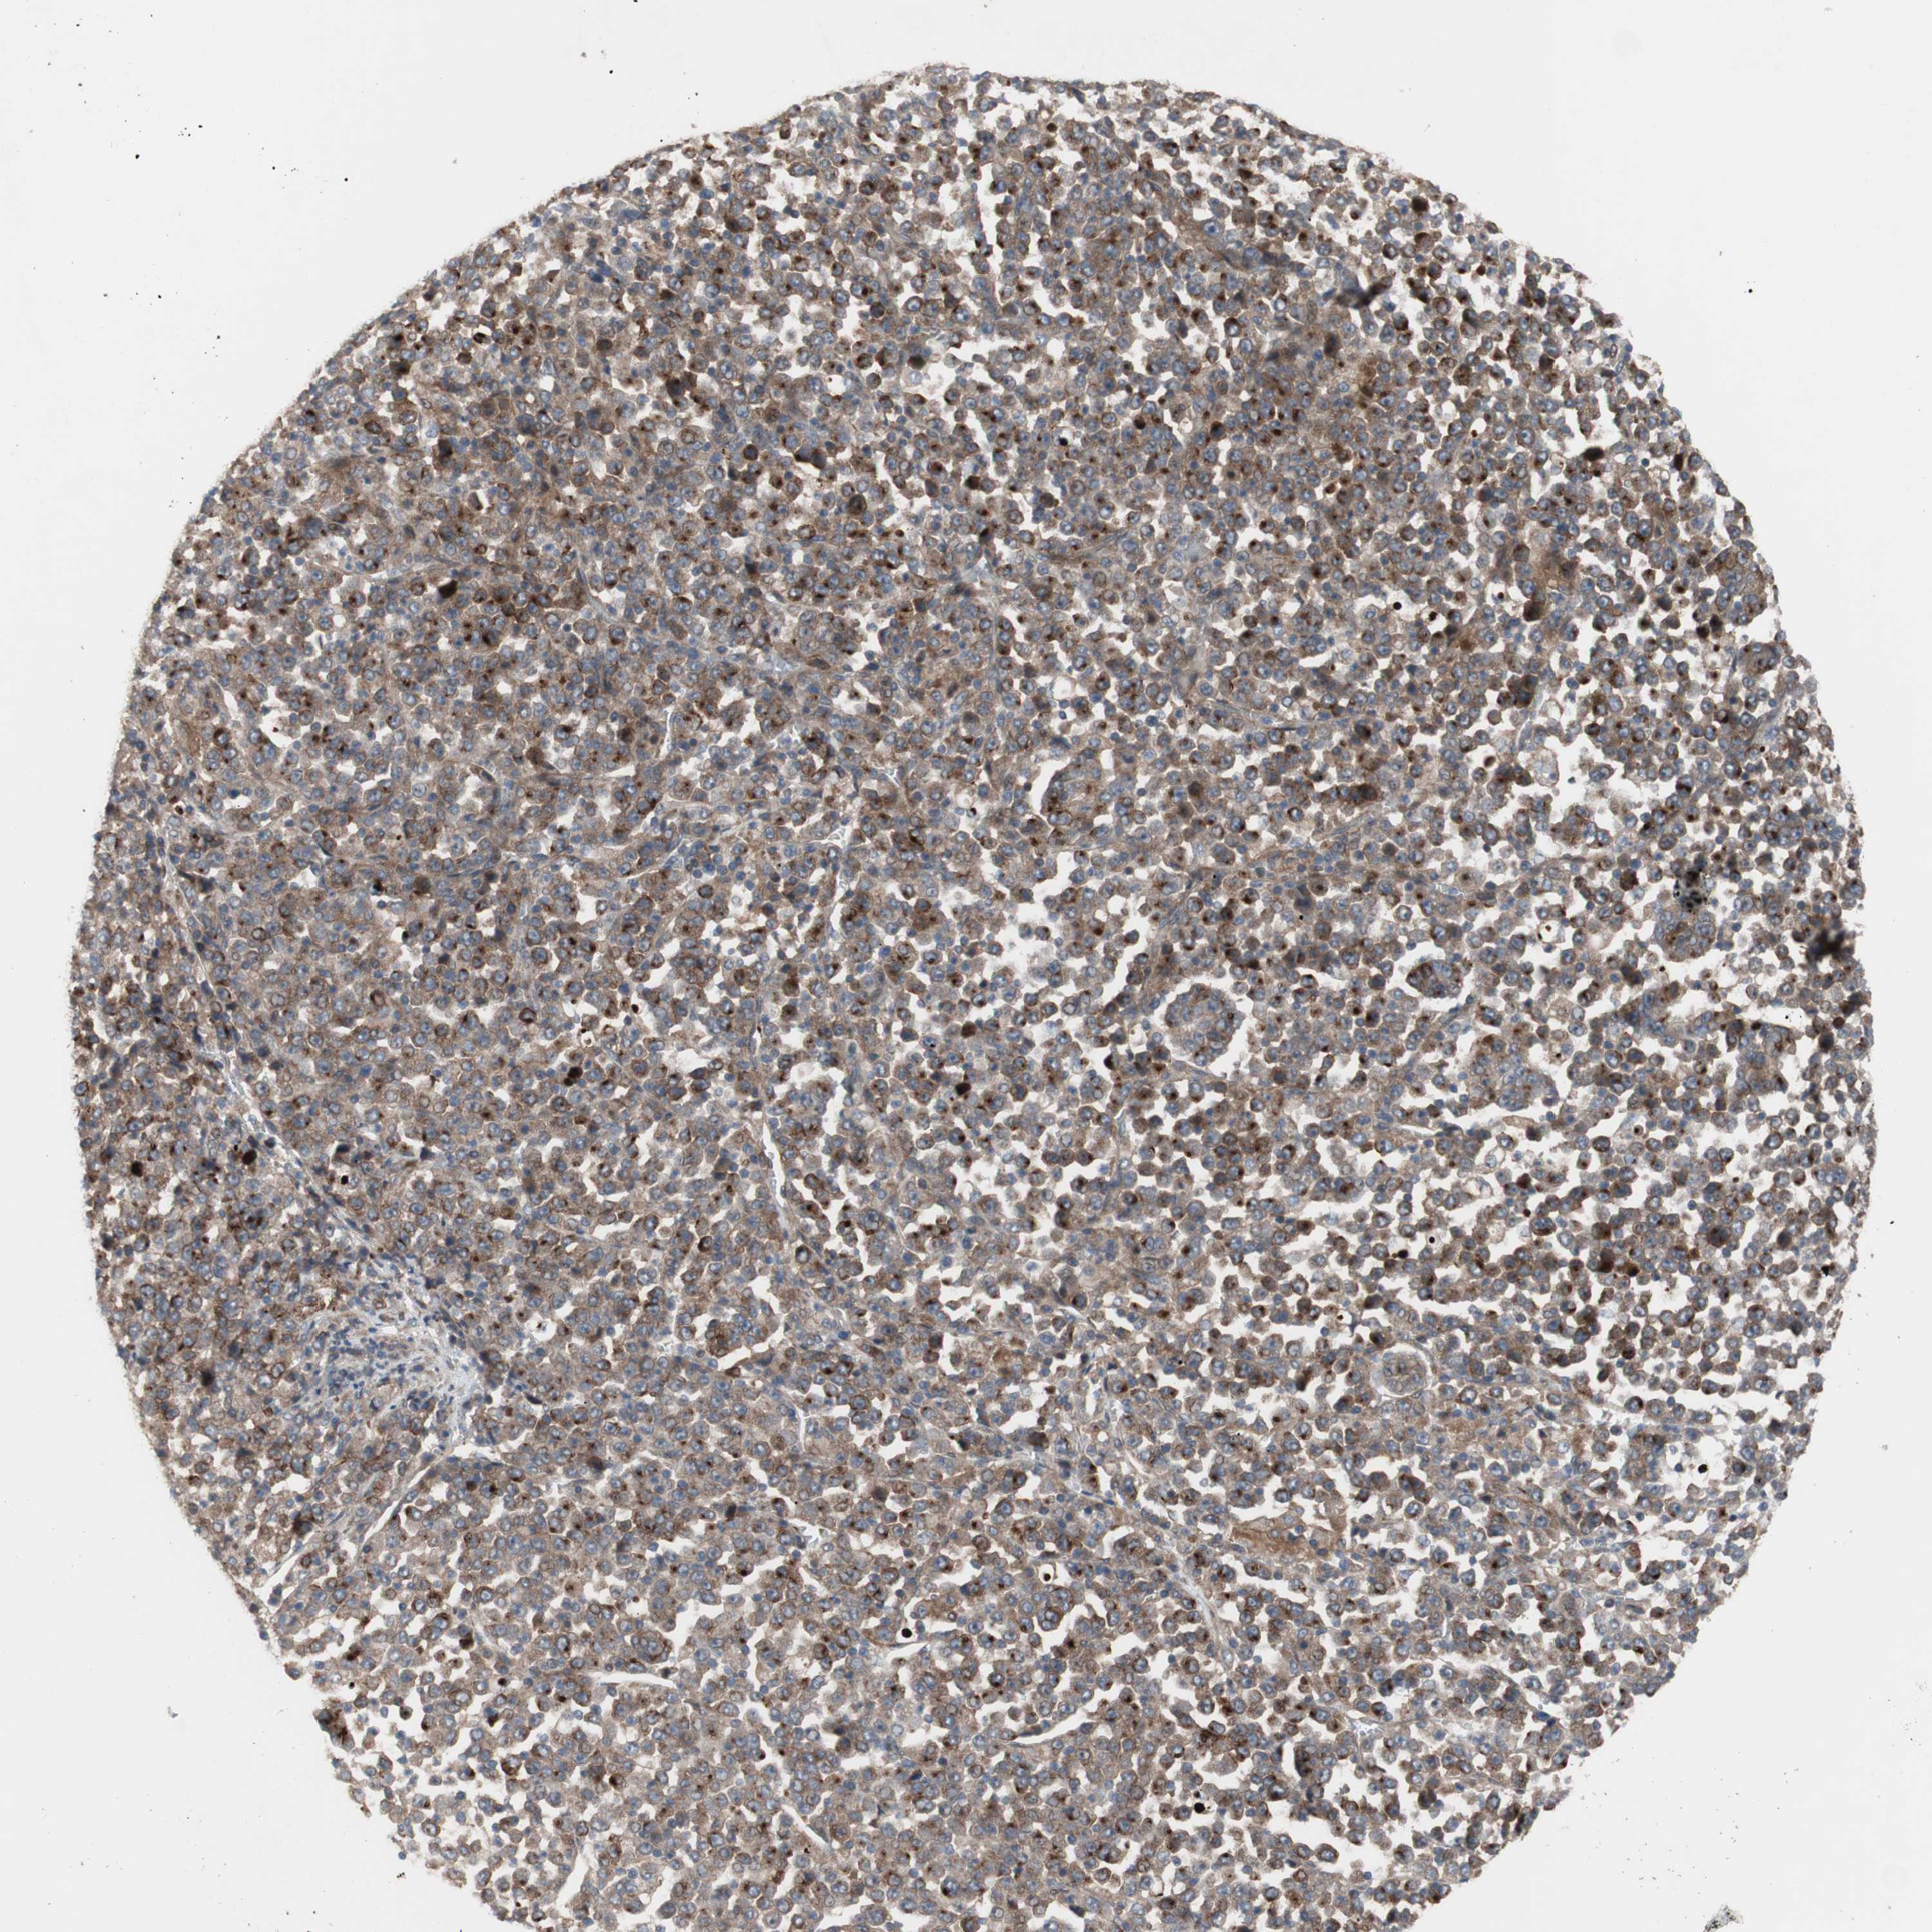

STOMACH CANCER - Protein expressioni

A mouse-over function shows sample information and annotation data. Click on an image to view it in a full screen mode. Samples can be filtered based on level of antibody staining by selecting one or several of the following categories: high, medium, low and not detected. The assay and annotation is described here.

Note that samples used for immunohistochemistry by the Human Protein Atlas do not correspond to samples in the TCGA dataset.

Antibody stainingi

Antibody staining in the annotated cell types in the current human tissue is reported as not detected, low, medium, or high, based on conventional immunohistochemistry profiling in selected tissues. This score is based on the combination of the staining intensity and fraction of stained cells.

Each image is clickable and will lead to virtual microscopy that enables deeper exploration of all samples and also displays staining intensity scores, fraction scores and subcellular localization as well as patient and tissue information for each sample.

Antibody HPA009291

Staining

High

Medium

Low

Not detected

Intensity

Strong

Moderate

Weak

Negative

Quantity

>75%

75%-25%

<25%

None

Location

Nuclear

Cytoplasmic/membranous

Cytoplasmic/membranous,nuclear

Adenocarcinoma, NOS